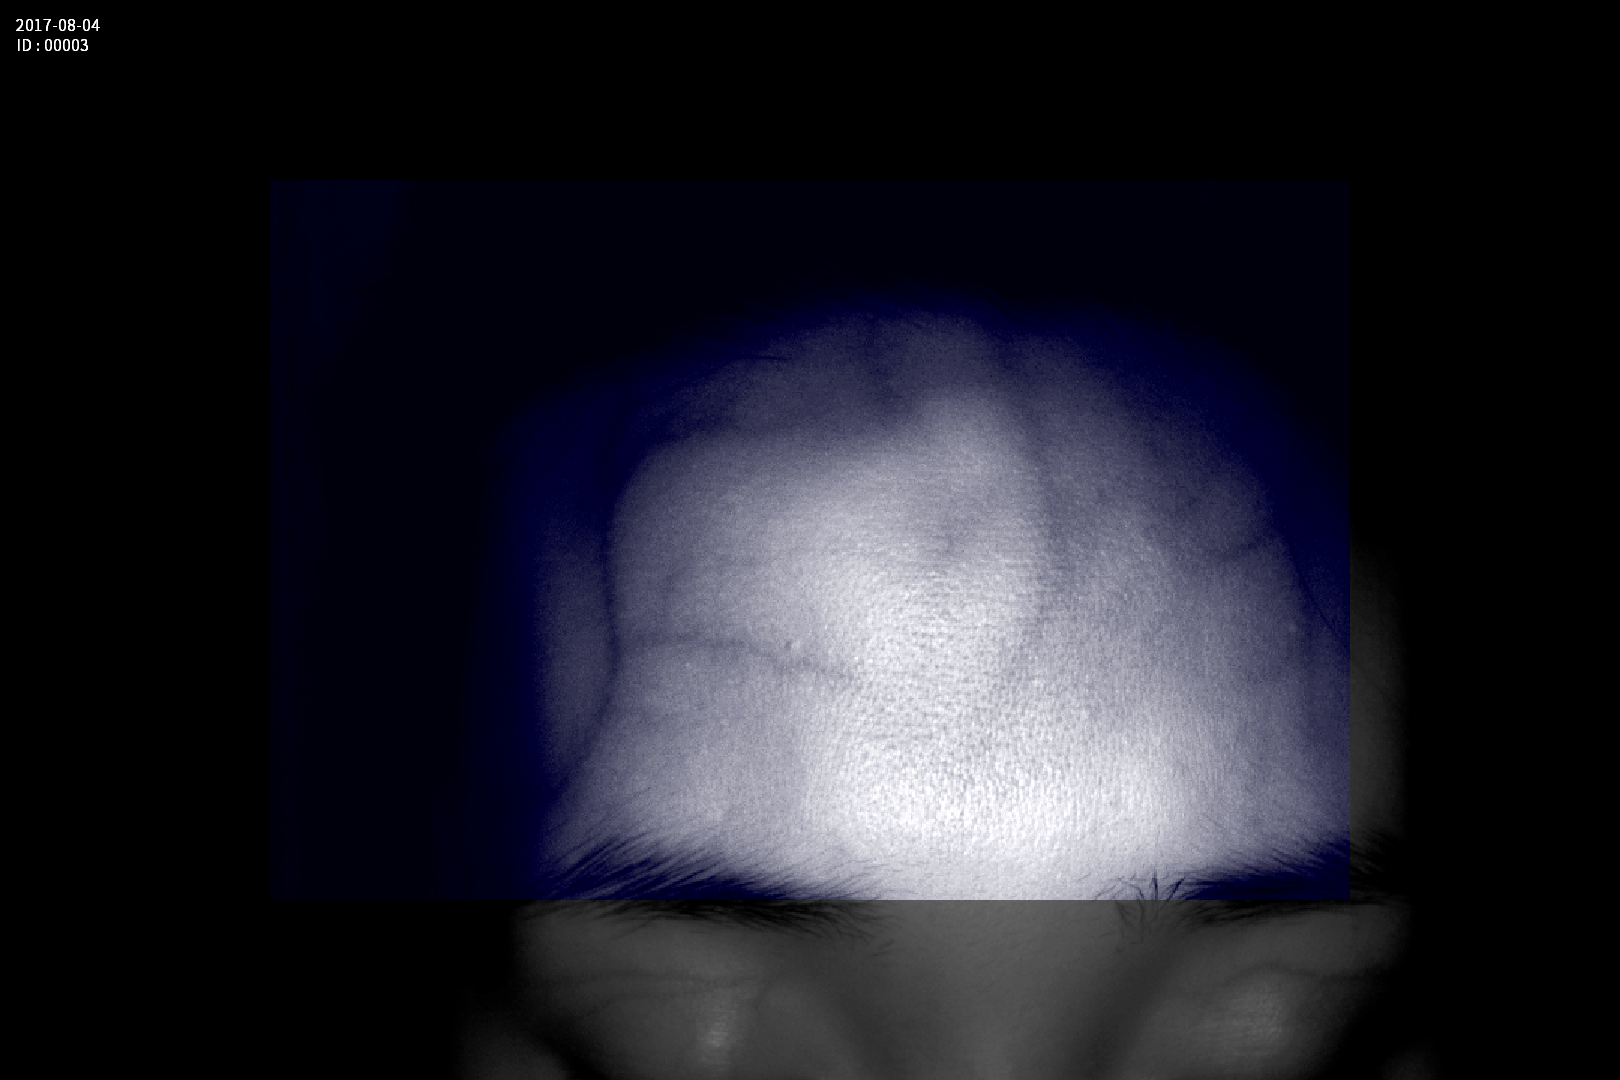

Dispozitiv medical portabil, non-contact, ce ajută la vizualizarea venelor pentru efectuarea puncției venoase, intervențiilor chirurgicale plastice, diagnosticul venelor varicoase.

Grad mare de detecție a venelor greu vizibile până la 10 mm adâncime (inclusiv vene faciale)

Imaginea venelor este proiectată pe monitorul propriu în timp real si ajută la identificarea corectă și precisă

Multiple aplicații de vizualizare vene atât la sugari cât și la pacienții obezi sau în urgențe indiferent de tonul de culoare a pielii